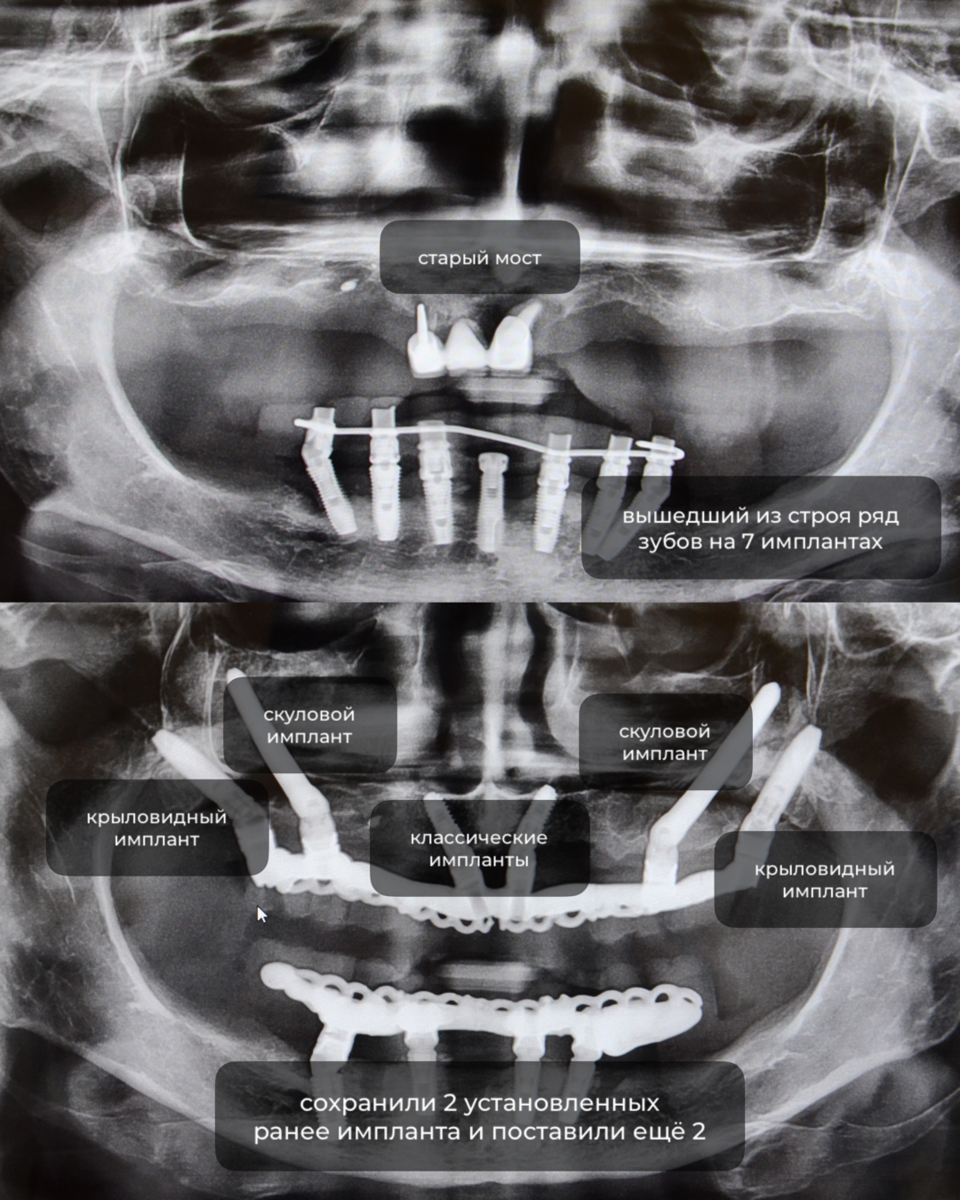

- полная адентия (отсутствие зубов)

- старый мост вместо передних зубов

- вышедший из строя ряд зубов на 7 имплантах

- сильный дефицит костной ткани

- на верхней челюсти All-on-6: 2 крыловидных, 2 скуловых и 2 классических импланта

- на нижней челюсти — All-on-4: сохранили 2 установленных ранее импланта и поставили ещё 2

до и после на снимке